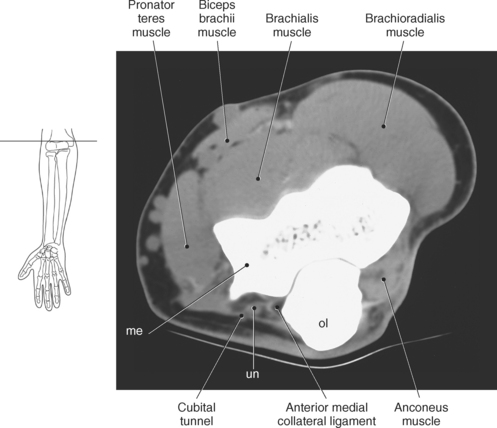

The elbow is a complex hinge-pivot joint created by the articulations of the humerus, radius, and ulna. All three articulations communicate with each other within a single joint capsule. The radius and ulna are the bones of the forearm, with the radius located on the lateral side. The radioulnar and radiohumeral articulations create the pivot joint that aids in supination and pronation of the elbow. The radiohumeral and ulnohumeral articulations form the hinge joint that allows for flexion and extension (Figures 9.70 through 9.73).

The distal portion of the humerus has two distinct prominences termed the medial and lateral condyles, with associated epicondyles, that provide attachment sites for tendons and ligaments (Figure 9.70). The medial epicondyle serves as the site of origin for the common flexor tendon, pronator teres muscle, and medial collateral ligament, whereas the lateral epicondyle serves as the attachment site for the common extensor tendon, supinator muscle, and lateral collateral ligament. Just lateral to the medial epicondyle along its posterior surface is a shallow groove containing the ulnar nerve. Two depressions located on the distal humerus are the anterior coronoid fossa and the deep posterior olecranon fossa. These depressions accommodate the coronoid and olecranon processes of the proximal ulna (Figures 9.70, 9.71, and 9.73). The distal humerus has two cartilage-covered articular surfaces—the capitellum and the trochlea for articulation with the radius and ulna (Figure 9.71). The lateral of the two surfaces is the capitellum, a rounded projection that articulates with the concave surface of the radial head. The trochlea is more medial and has the appearance of an hourglass if viewed in the horizontal plane. The shape of the trochlea helps keep the ulna in position during flexion between the distal humerus and proximal radius (Figure 9.73).

The stability of the elbow joint primarily depends on the collateral ligaments that are woven into the lateral portions of the joint capsule. The ulnar collateral ligament (medial collateral ligament) consists of three components: an anterior band, a posterior band, and a transverse band (ligament of Cooper) (Figures 9.79 through 9.82). The anterior band, which is the strongest, extends from the medial epicondyle of the humerus to the medial aspect of the coronoid process. The posterior band originates along with the anterior band from the medial epicondyle of the humerus and inserts on the medial aspect of the olecranon process, forming a triangular plate. The weaker transverse band stretches between the medial surfaces of the coronoid and olecranon processes to unite the anterior and posterior bands. Reinforcing the lateral side is the triangular radial collateral ligament (lateral collateral ligament). The radial collateral ligament originates from the lateral epicondyle of the humerus, adjacent to and beneath the common extensor tendons, and spreads distally to insert on the annular ligament and the anterior and posterior margins of the radial notch of the ulna (Figures 9.81 and 9.83). The annular ligament forms a fibrous ring that encircles the radial head, with a narrow portion that tightens around the radial neck to prevent inferior displacement of the radius (Figures 9.79 and 9.83 through 9.85). The annular ligament is considered a key structure in the proximal radioulnar joint, allowing the head of the radius to rotate freely. Just distal to the annular ligament is the quadrate ligament, a small band of tissue that passes from the radial notch of the ulna to the neck of the radius to provide stability to the joint during supination and pronation.

The brachial plexus, also described in Chapter 4, is a large network of nerves that innervate the upper limb (Figures 9.38 and 9.148). It extends from the neck into the axilla. The brachial plexus is formed by the union of the ventral rami of nerves C5-C8 and the greater part of the T1 ventral ramus. The ventral rami from C5 and C6 unite to form a superior trunk, the ventral ramus of C7 continues as the middle trunk, and the ventral rami of C8 and T1 unite to form an inferior trunk. Each of these trunks divides into an anterior and posterior division. The anterior divisions supply the anterior (flexor) parts of the upper limb, and the posterior divisions supply the posterior (extensor) parts of the upper limb. These divisions form three cords (posterior, lateral, and medial) that continue to divide to form the median, ulnar, musculocutaneous, and radial nerves (sequential Figures 9.59 through 9.67 and 9.87 through 9.95). These nerves supply the muscles of the forearm and hand. The median nerve descends the cubital fossa deep to the median cubital vein. It supplies the pronator teres muscle of the arm and all the superficial and deep flexor muscles of the forearm, except the flexor carpi ulnaris muscle. It gives off an anterior interosseous branch that descends within the forearm to supply the flexor digitorum profundus muscle. The median nerve courses through the carpal tunnel of the wrist, typically superficial to the flexor tendons (Figure 9.147). It supplies flexors of the hand, skin of the wrist, thenar eminence, palm of the hand, and sides of the first three digits and lateral half of the fourth. At the elbow, the ulnar nerve passes between the medial epicondyle of the humerus and the olecranon process within the cubital tunnel to enter the medial side of the flexor compartment of the forearm (Figure 9.148). Posterior to the medial epicondyle, the ulnar nerve is superficial and easily palpable. It supplies the flexor carpi ulnaris muscle and the medial side of the flexor digitorum profundus muscle in the forearm before entering the hand. The ulnar nerve passes under the flexor retinaculum, along with the ulnar artery, to enter the palmar compartment of the hand (Figure 9.147). At this point, the ulnar nerve divides into superficial and deep terminal branches that supply the ulnar flexors of the hand as well as the skin on the medial side of the palm, medial half of the dorsum of the hand, fifth digit, and medial half of the fourth digit. The musculocutaneous nerve descends to the lateral side of the arm and elbow to innervate the flexors in the arm and the skin of the forearm, wrist, and thenar region of the hand (Figure 9.146). It emits branches that supply both heads of the biceps brachii muscle, the brachialis muscle, and the elbow joint. It innervates the skin of the dorsal surface of the arm. A continuation of the musculocutaneous nerve is the lateral cutaneous nerve, which terminates into cutaneous branches that supply the skin covering the radial side of the wrist and the thenar eminence. The radial nerve is the largest branch of the brachial plexus. It passes inferolaterally around the body of the humerus in the radial groove (Figure 9.146). It continues inferiorly between the brachialis and brachioradialis muscles to the level of the lateral epicondyle of the humerus, where it divides into deep and superficial branches. The deep branches supply all the extensors in the arm and forearm, and the cutaneous branches innervate the skin on the dorsal side of the arm and hand. The superficial branch, the direct continuation of the radial nerve, is entirely sensory. It supplies skin and fascia over the lateral two thirds of the dorsum of the hand, the dorsum of the thumb, and proximal parts of the lateral three and one half digits on their dorsal surfaces (Figures 9.57 through 9.67, 9.87 through 9.98, and 9.146 and 9.147).